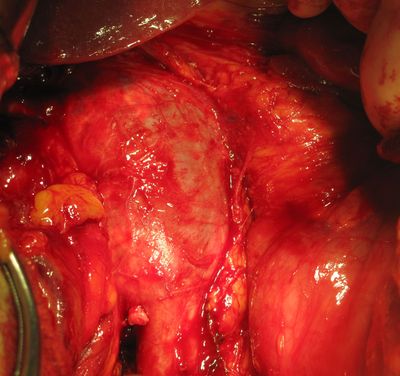

Мобилизованная вена с тромбом